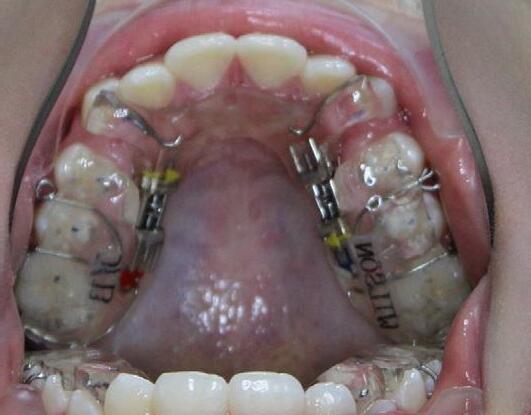

Maxillary and mandibular impressions were taken in irreversible hydrocolloid impression material. Both TMJ discs were recaptured in the Phonetic bite,6 which was recorded with the PVS bite recording material (Blue Bite). The therapeutic splint was fabricated, tried, inserted, and verified that the displaced discs were recaptured. This splint must be worn 24/7, except brushing the teeth, eating and sports (6-A, B, C, D, E).

After the patient became accustomed wearing the splint, the acrylic was cut off distally to #46(30) and #36(19). A band was cemented on #17(2), #16(3) and #27(15), #26(14) and brackets/ tubes were bonded on #15(4), #25(13), #37(18), and #47(31). A 016 SS sectional wire was inserted in the maxilla bilaterally from the second molar to the second bicuspid and a ¼” - 4.5 oz elastics were placed for forced eruption of the mandibular second molars (Figure 7-A, B).

When the mandibular second molars became in contact with the maxillary molars, the acrylic was hollowed out from the intaglio of the splint above #46(30) and #36(19). Two ¼” –4.5 oz triangular elastics were placed for forced eruption of the mandibular first and second molars (Figure 7-C, D).

After the mandibular second molars became firmly in contact with the maxillary molars, a Maxillary removable protrusive appliance (Twin block II) with hooks was inserted to maintain the therapeutic position with the recaptured disks. Also, composite build-up was bonded to the lingual surface of #11(8) and #21(9), to maintain the mandible in the same position. Three ¼” – 4.5 oz triangular elastics were placed for forced eruption of the mandibular first molars and bicuspids. Separators were placed between the mandibular molars and bicuspids to speed up the elevation of the posterior sextants (figure 7-E, F, G).